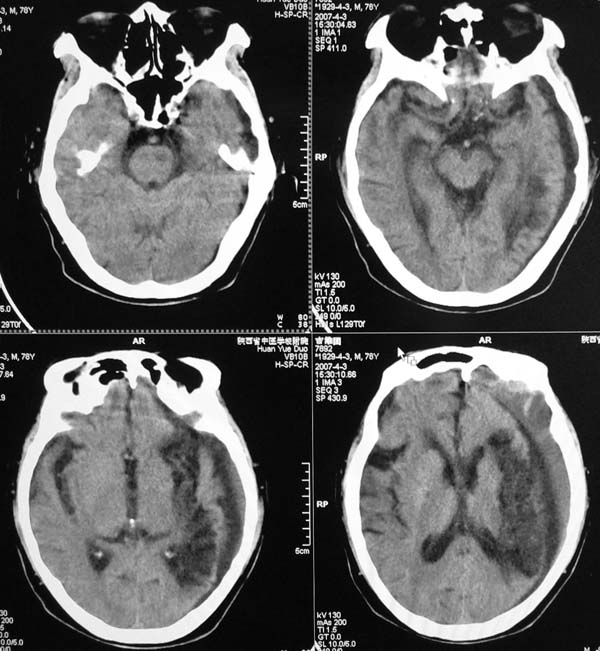

以下是引用star--868在2007-6-15 20:54:00的发言:[br]1.左侧额颞顶部亚急性硬膜下血肿并继续出血 双侧额颞顶部硬膜下积液;[br]2.左颞枕叶、左基底节区脑软化-左侧大脑中动脉栓塞;[br]双侧额颞顶部硬膜下积液应和治疗期间应用高渗脱水剂相鉴别:停用甘露醇后硬膜下积液会逐渐吸收减少,而单纯硬膜下积液无此改变和/或逐渐增多。

以下是引用狙击手在2007-6-15 21:15:00的发言:[br]软化灶就不必说了,主要是混和性血肿的渐变过程。

以下是引用老爱克斯新网客在2007-6-15 20:40:00的发言:[br]1左侧颞叶软化灶,2双侧硬膜下水瘤,3左册硬膜下血肿(多次少量出血),

以下是引用还珠格格在2007-6-16 7:07:00的发言:[br]支持.左侧额颞顶部亚急性硬膜下血肿并继续出血 双侧额颞顶部硬膜下积液;[br]2.左颞枕叶、左基底节区脑软化-左侧大脑中动脉栓塞;